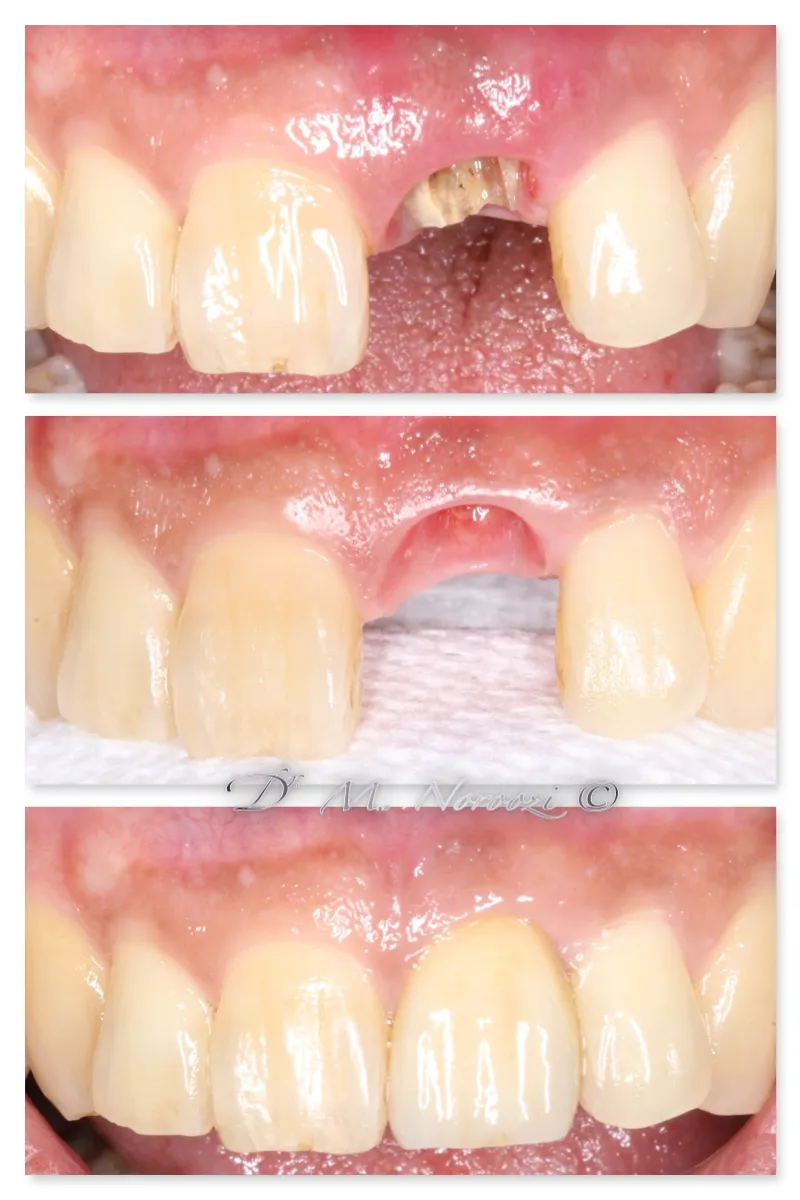

Before & Afters of Dental Implant Patients

Complete Dental Implant Cases Gallery

Surgical advances with SAME-DAY IMPLANTS in Vancouver BC

Using the most recent advances in dental implant technology, Dr. Noroozi is able to place single stage implants. These implants do not require a second procedure to uncover them but may require a minimum of six weeks of healing time before artificial teeth are placed. There are even situations where the implant can be placed at the same time as the tooth extraction and the artificial tooth can be inserted immediately following the implant placement – further minimizing your number of surgical procedures.

General Disclaimer: The results in the photographs are examples only and do not imply any certainty of the result of a procedure, and all outcomes are subject to the circumstances of the individual patient.